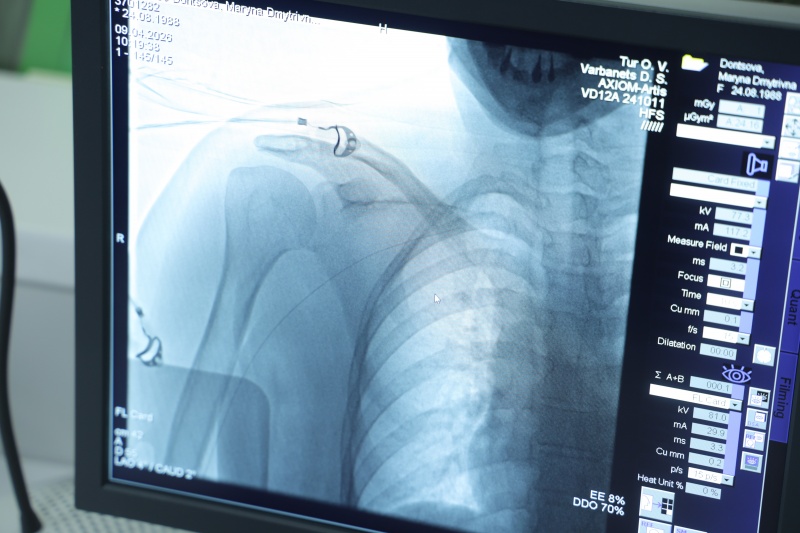

Операция, которую вы сейчас видите – это тоже хирургическое вмешательство, но малоинвазивное (с минимумом разрезов – ред.). Сейчас мы с вами разговариваем в операционном отделении. Мы находимся возле изолированного помещения, где за защитным стеклом видно, как врачи проводят стентирование (когда в суженный сосуд ставят маленький каркас – стент, чтобы расширить его и восстановить нормальный кровоток. Обычно сосуды сужаются из-за атеросклеротических бляшек – ред.)

Врачи, медсестры, одеты в специальные защитные халаты. Это бережет персонал от ионизирующего облучения, поскольку вмешательство проводится под рентгеновскими лучами. Для пациента это тоже не очень приятно и комфортно. Но для пациента, я надеюсь, это единственный такой опыт, в то время как для врачей это может быть и 10-15 раз в день.

В операционной центра кардиологии и кардиохирургии проводят операции стентирования под рентгенологическим контролем (фото: РБК-Украина)